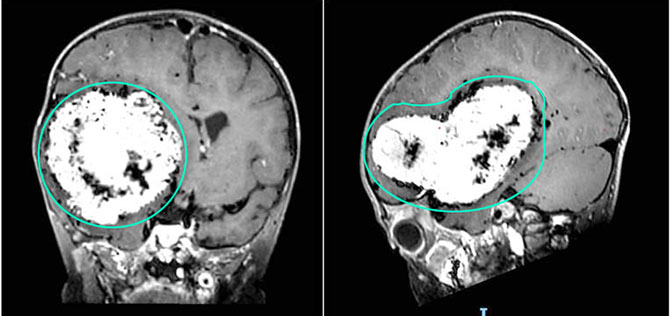

经头部MR增强检查,发现患儿右侧大脑半球有一个巨大的肿瘤,直径约10厘米,严重压迫周围正常脑组织,病情十分危急。

在团队的通力合作下,肿瘤最终被完整切除,切除组织大小约13×7×4厘米,病理显示这是一个脑膜瘤。